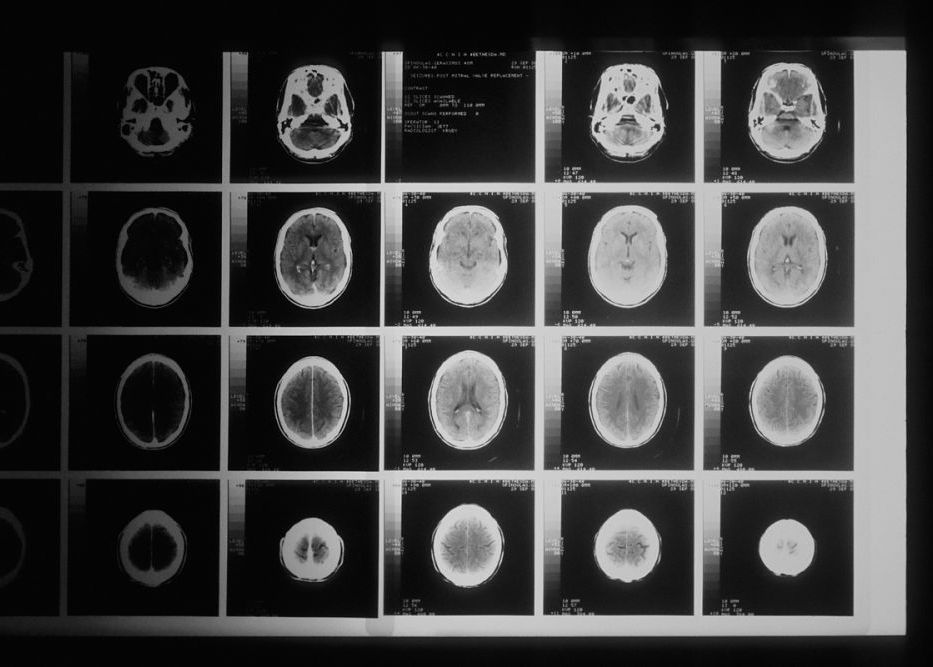

Vaccinul care are potențialul de a trata tumorile cerebrale

Primul vaccin din lume pentru tratarea tumorilor cerebrale canceroase maligne le poate oferi pacienților ani de viață în plus, potrivit concluziilor unui studiu clinic realizat la nivel mondial.